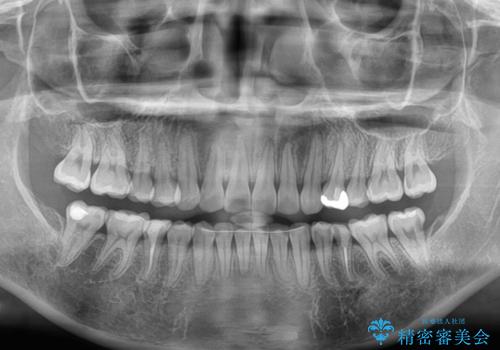

開咬と前方に飛び出した前歯 インビザラインによる矯正治療

舌の突出癖改善のトレーニングをしっかりと行っていただき、上下前歯が接触する咬み合わせを達成することができました。